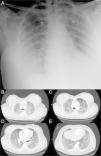

On admission patient had Glasgow Coma Scale Score of 15, tachypnea and tachycardia, with central cyanosis and was sweating. No fever. Blood pressure was 100/70mmHg and respiratory rate 40/min. Arterial blood gas analysis under 15l/min oxygen therapy by a non-rebreathing mask with reservoir showed global respiratory insufficiency and sever acidemia (pH 7.22, pO2 31mmHg, pCO2 49mmHg, HCO3− 17.6mEq/L, SatO2 55%, lactate 6.17mmol/L). Heart auscultation revealed audible S1 and S2 and chest auscultation revealed bilateral rales. The remaining physical examination just was unremarkable with exception of mild redness, warmth and swelling of the gluteus. No fluctuation was detected and no indication for surgical approach was considered. Chest X-ray showed bilateral lung infiltrates (Fig. 1A). At this time was intubated and mechanically ventilated.

Electrocardiogram showed sinus tachycardia with S1Q3T3 pattern. Computed tomography angiography ruled out pulmonary embolism and disclosed bilateral consolidations with air-bronchograms and ground-glass-appearing opacities suggestive of alveolar damage (Fig. 1B–E). Transthoracic echocardiogram revealed normal left ventricular systolic function with no contractility alterations, valve dysfunctions or pericardial effusion.

Chest CT with significant reduction of pulmonary infiltrates. Laboratory tests evidenced recovery of hepatic function with correction of the coagulation disorder.